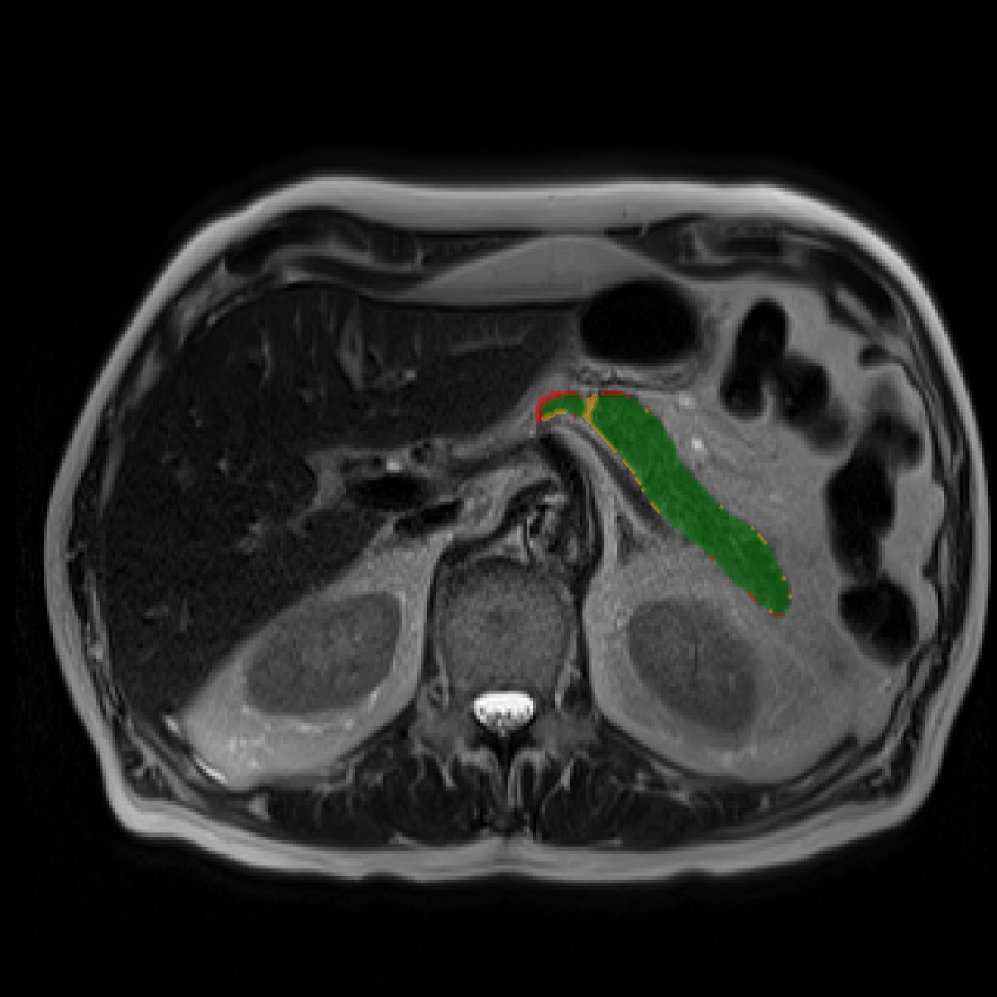

Accurate pancreas segmentation is a critical prerequisite for precise cyst analysis and classification. Recently, we developed PanSegNet [zhang2025large], a novel segmentation architecture incorporating linear self-attention layers [zhang2022dynamic] within the nnUNet framework [isensee2021nnu] to enhance global information modeling capabilities while maintaining computational efficiency (Fig. 1). PanSegNet demonstrated exceptional segmentation performance across both T1W and T2W modalities, achieving mean dice scores of 86.817.30% and 89.626.38%, respectively (Table 1, Fig. 2b-c). This performance significantly exceeded that of Swin-UNETR [hatamizadeh2021swin], one of the most used state-of-the-art transformer-based medical segmentation models, which achieved dice scores of 79.091.40% and 76.290.66% for T1W and T2W, respectively (). In this study, we integrated PanSegNet into our Cyst-X engine along with a classifier for risk prediction. In Section 2.2, we show that the choice of segmentation model affects the classification results. The performance advantage of PanSegNet was consistent across all seven medical centers, demonstrating robust generalization despite variations in imaging protocols and equipment (Table 1). This cross-institutional reliability is particularly important for clinical applications, where model performance must remain consistent regardless of imaging site or acquisition parameters.

Each patient was categorized into one of these three ground truth classes: no risk/control, IPMN low-risk, or IPMN high-risk. To evaluate variability in image acquisition, we applied uniform manifold approximation and projection (UMAP) to image quality indicators, revealing distinct clustering patterns by imaging center and slice thickness. This heterogeneity reflects real-world clinical variability, enhancing the dataset’s generalizability while presenting technical challenges for model development. Fig. 6 shows examples of low-grade, high-grade, and cancer developing IPMNs from the Cyst-X dataset.